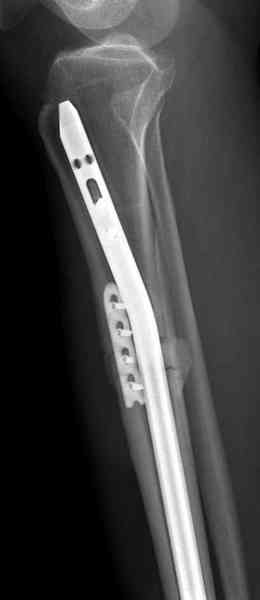

Недавно на нашей ежемесячной Morbidity&Mortality conference мы

разбирали похожий случай, ложный сустав большеберцовой кости после

резекции опухоли.

К нашему онкологу-ортопеду обратился больной с жалобами на боли в

голени, из рассказа - год назад была сделана биопсия большеберцовой

кости, но название заболевания "не запомнил".

Оперирован в военном госпитале с заменой сегмента аллокостью

большеберцовой кости и после демобилизации явился для постоянного

наблюдения по месту жительства.

Наши имели проблему со сращением, пришлось им сделать динамизацию,

дополнительную аутопластику.

Снимки представлены.

Имя     : 1 adamantioma ap orig.jpg